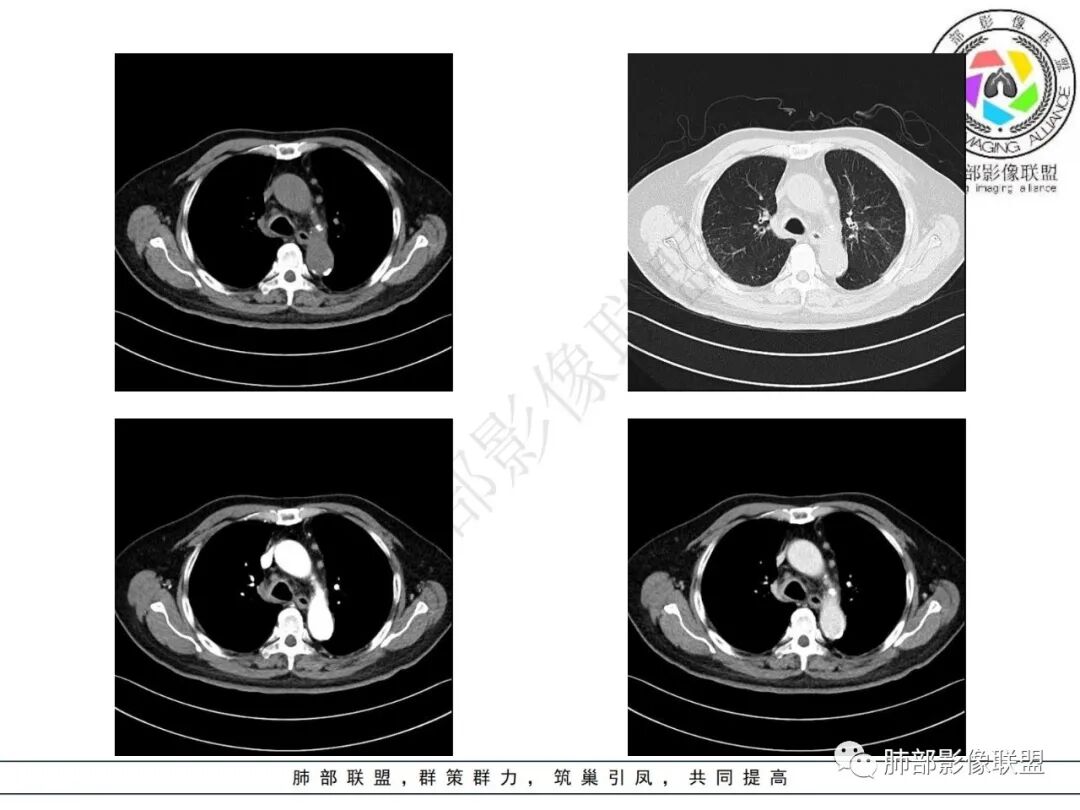

2.影像表现:双肺上叶见结节影及条索影,树丫等,边界可分辨。气管支气管壁广泛增厚、钙化,形态相对均匀一致,上达声门区。支气管膜部受累。增强轻中度强化。纵隔见轻度增大淋巴结。

3.综合分析:双肺上叶病灶较符合继发性肺结核。支气管病变分布具有广泛性、一致性。支气管壁广泛增厚钙化常见于淀粉样变性。累及膜部气管支气管病变的有淀粉样变性和GPA